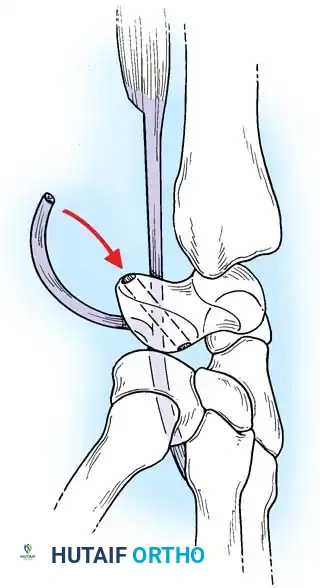

Closed reduction with percutaneous pinning (placing 0.045-inch K-wires from the scaphoid to the capitate and lunate) can be attempted. However, open reduction through a dorsal approach is generally preferred. This allows direct closure of the scapholunate gap, K-wire fixation, and primary repair of the dorsal SL interosseous ligament using suture anchors.